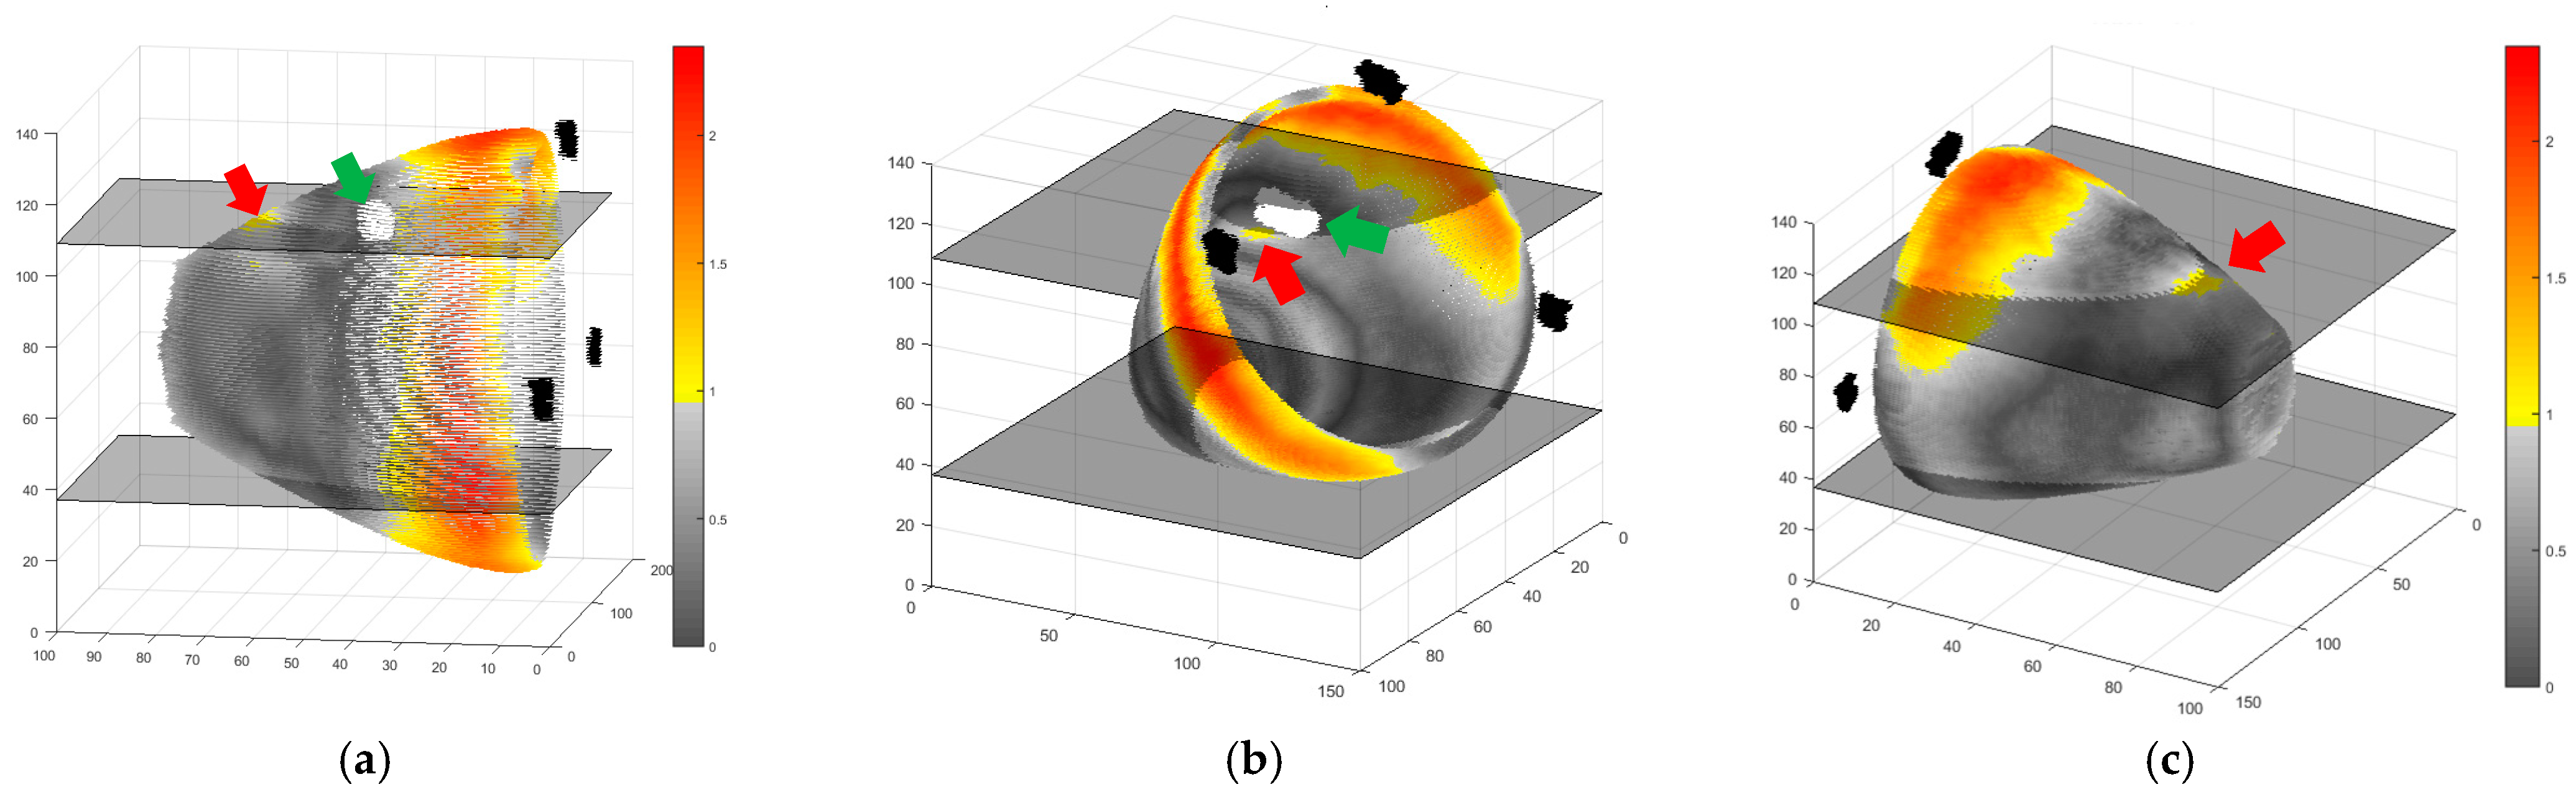

2. Results and Discussion

4. Materials and Methods